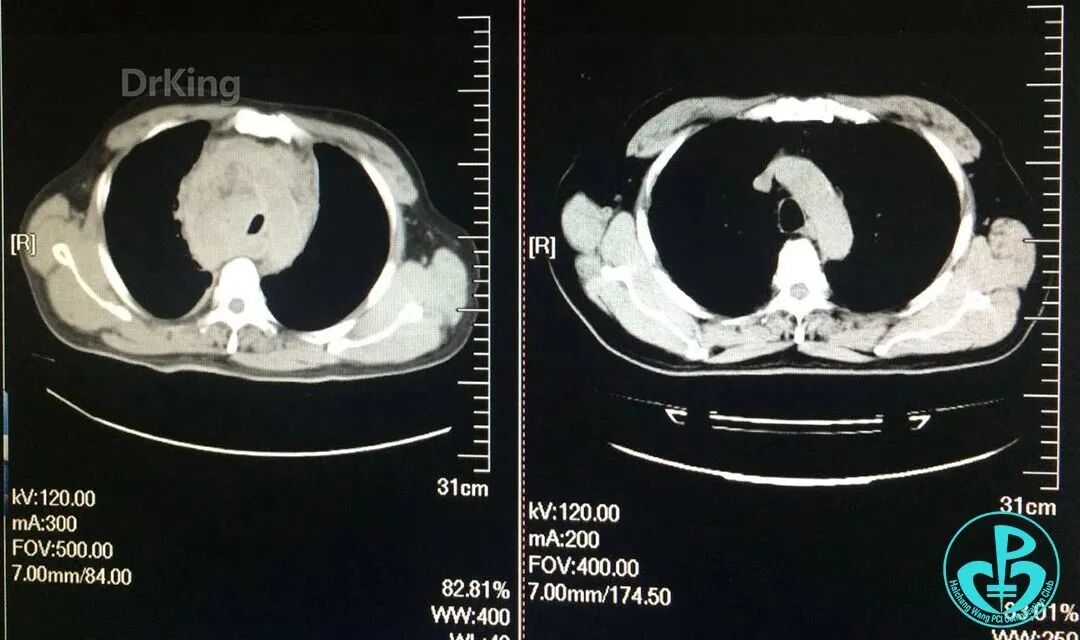

入院前急诊肺CT与术后2小时胸部CT对照,术后发生纵隔血肿。

泥鳅导丝怎么用超滑泥鳅导丝致纵隔血肿,保守治疗血肿吸收_https://www.jmylbn.com_新闻资讯_第13张